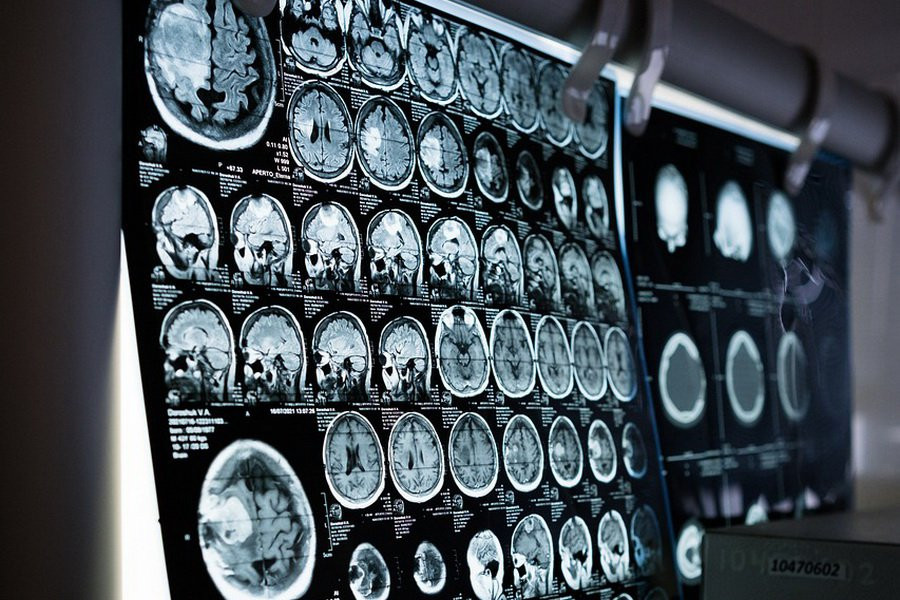

Создание первой автономной системы глубокой стимуляции мозга стало результатом длительных наблюдений за 17 добровольцами, страдающими болезнью Паркинсона. Участникам исследования были имплантированы электроды в глубинные области мозга, что позволило ученым отслеживать изменения в работе нервной системы во время различных повседневных действий как при наличии стимуляции, так и без нее.

В ходе исследования были выявлены характерные изменения в работе гамма-ритмов в моторной коре мозга и в ядре субталамуса, которые возникали в периоды наиболее выраженных симптомов заболевания. Среди этих симптомов были брадикинезия (замедленная реакция конечностей на желание совершить движение), дистония (непроизвольные сокращения мышц) и другие проявления болезни Паркинсона.